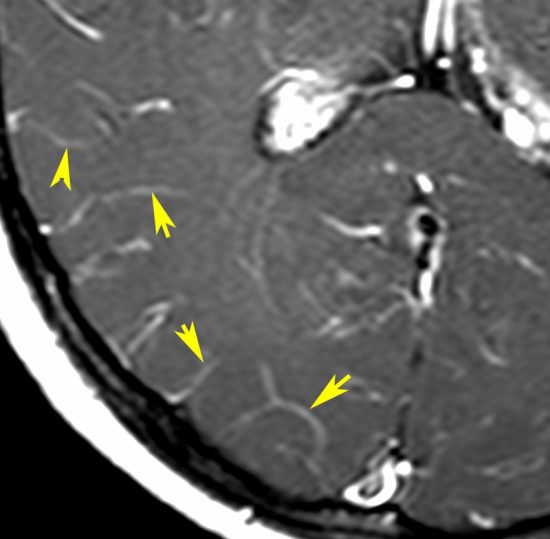

髄膜癌腫症(癌性髄膜炎)

leptomeningeal carcinomatosis, carcinomatous meningitis

脳と脊髄の表面にがん細胞が広範に広がって増殖します。MRIでは,矢印のように脳溝 sulciの中に癌の増殖が見られます。T1ガドリニウム増強で,脳溝や脳の表面が白い線のように描出されます,脳血管とは違うのでわかります。